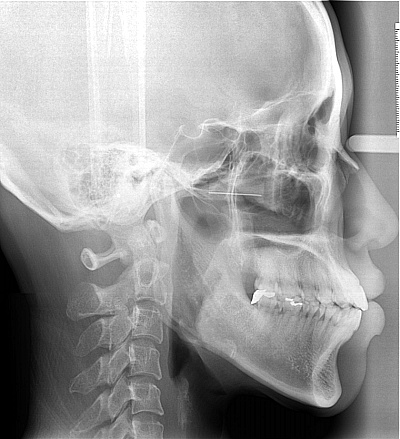

돌출 개선될 수 있을까요

철사맨 선생님 안녕하세요~^^ 전부터 돌출된 입이 컴플렉스 였어요. 나이 드니까 더 두드러지는것 같아 속상하고 주위에서도 입을 가려야 이쁘다고 하고 ㅠㅠ 30대 초반인데 그동안 생각만 하고 있던 교정을 더 늦기...

전문의 답변 1